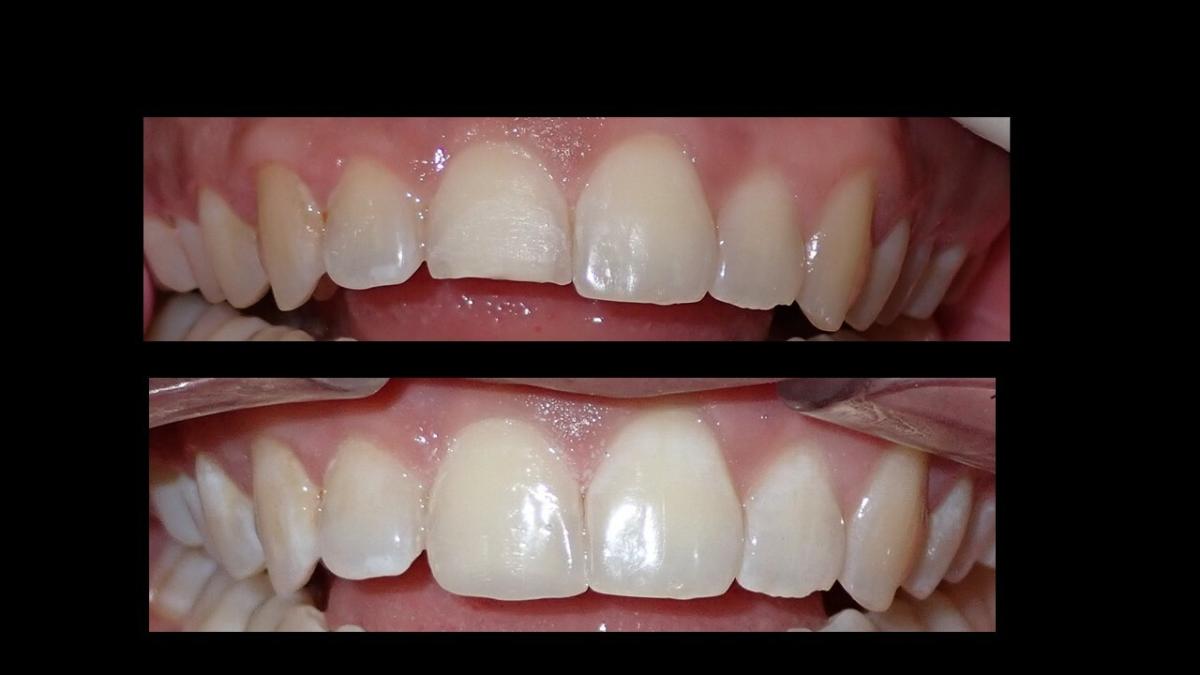

large-Fractura con resina

large-Fractura